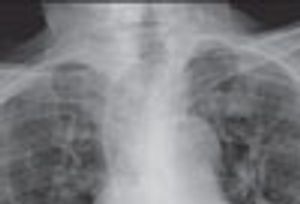

An 88-year-old woman was brought to the emergency department after she choked on a piece of meat. She had dysphagia of many years’ duration and progressive weight loss over the past 5 years.